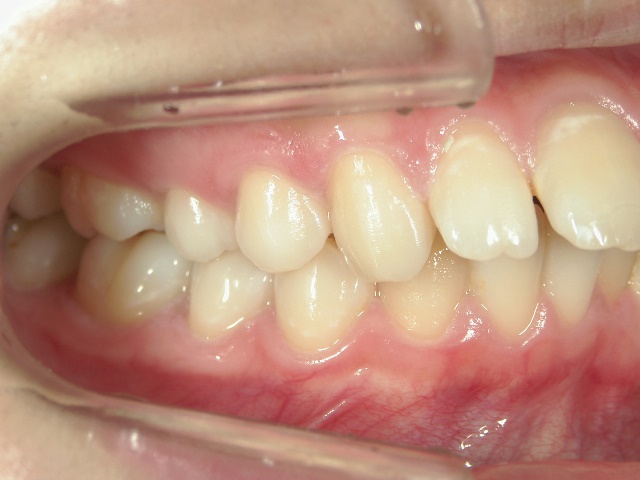

矯正歯科 治療前